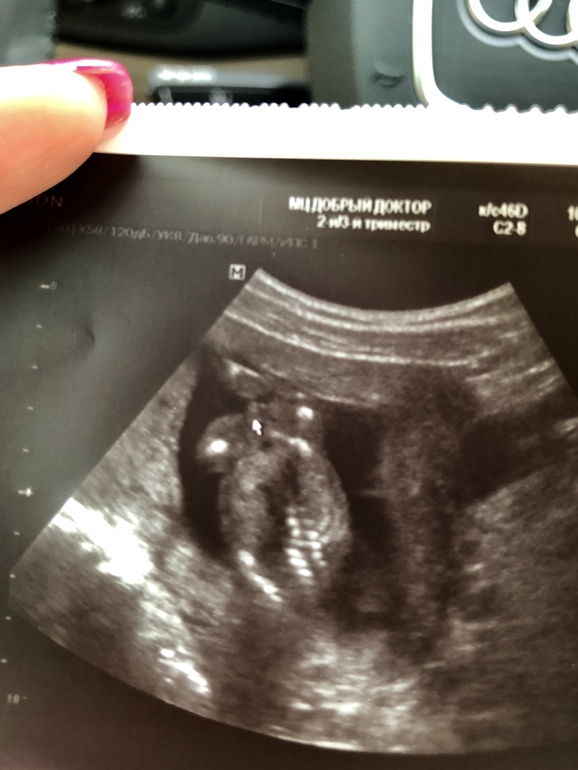

УЗИ, КТГ, доплерБыло новое узи, с другим врачем, на другом аппарате, в другом центре. Качество изображения оставляет желать лучшего.

Полторы недели назад на узи увидели девочку, а сейчас (16 нед ровно) якобы мальчик 🤷🏼♀️ Но! Врач мне показывала-показывала мужские достоинства торчащие из под попы, но мне, честно, показалось это бредом, все как- то не очевидно и лишь бы что сказать. Как вам кажется ? Ребёнок, как я понимаю, спиной к датчику, попой вверх и вот там, где стрелочка якобы показываются «они», у девочки, говорит, ничего бы не было вообще. Там ещё пуповина между ног, конечно же. Поэтому это был лучший для врача ракурс)